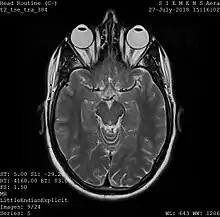

Magnetic resonance imaging

One frame of an MRI scan of the head showing the eyes and brain.

A magnetic resonance imaging instrument (MRI scanner), or "nuclear magnetic resonance (NMR) imaging" scanner as it was originally known, uses powerful magnets to polarize and excite hydrogen nuclei (i.e., single protons) of water molecules in human tissue, producing a detectable signal which is spatially encoded, resulting in images of the body.[5] The MRI machine emits a radio frequency (RF) pulse at the resonant frequency of the hydrogen atoms on water molecules. Radio frequency antennas ("RF coils") send the pulse to the area of the body to be examined. The RF pulse is absorbed by protons, causing their direction with respect to the primary magnetic field to change. When the RF pulse is turned off, the protons "relax" back to alignment with the primary magnet and emit radio-waves in the process. This radio-frequency emission from the hydrogen-atoms on water is what is detected and reconstructed into an image. The resonant frequency of a spinning magnetic dipole (of which protons are one example) is called the Larmor frequency and is determined by the strength of the main magnetic field and the chemical environment of the nuclei of interest. MRI uses three electromagnetic fields: a very strong (typically 1.5 to 3 teslas) static magnetic field to polarize the hydrogen nuclei, called the primary field; gradient fields that can be modified to vary in space and time (on the order of 1 kHz) for spatial encoding, often simply called gradients; and a spatially homogeneous radio-frequency (RF) field for manipulation of the hydrogen nuclei to produce measurable signals, collected through an RF antenna.

Like CT, MRI traditionally creates a two-dimensional image of a thin "slice" of the body and is therefore considered a tomographic imaging technique. Modern MRI instruments are capable of producing images in the form of 3D blocks, which may be considered a generalization of the single-slice, tomographic, concept. Unlike CT, MRI does not involve the use of ionizing radiation and is therefore not associated with the same health hazards. For example, because MRI has only been in use since the early 1980s, there are no known long-term effects of exposure to strong static fields (this is the subject of some debate; see 'Safety' in MRI) and therefore there is no limit to the number of scans to which an individual can be subjected, in contrast with X-ray and CT. However, there are well-identified health risks associated with tissue heating from exposure to the RF field and the presence of implanted devices in the body, such as pacemakers. These risks are strictly controlled as part of the design of the instrument and the scanning protocols used.

Because CT and MRI are sensitive to different tissue properties, the appearances of the images obtained with the two techniques differ markedly. In CT, X-rays must be blocked by some form of dense tissue to create an image, so the image quality when looking at soft tissues will be poor. In MRI, while any nucleus with a net nuclear spin can be used, the proton of the hydrogen atom remains the most widely used, especially in the clinical setting, because it is so ubiquitous and returns a large signal. This nucleus, present in water molecules, allows the excellent soft-tissue contrast achievable with MRI.

A number of different pulse sequences can be used for specific MRI diagnostic imaging (multiparametric MRI or mpMRI). It is possible to differentiate tissue characteristics by combining two or more of the following imaging sequences, depending on the information being sought: T1-weighted (T1-MRI), T2-weighted (T2-MRI), diffusion weighted imaging (DWI-MRI), dynamic contrast enhancement (DCE-MRI), and spectroscopy (MRI-S). For example, imaging of prostate tumors is better accomplished using T2-MRI and DWI-MRI than T2-weighted imaging alone.[6] The number of applications of mpMRI for detecting disease in various organs continues to expand, including liver studies, breast tumors, pancreatic tumors, and assessing the effects of vascular disruption agents on cancer tumors.[7][8][9]